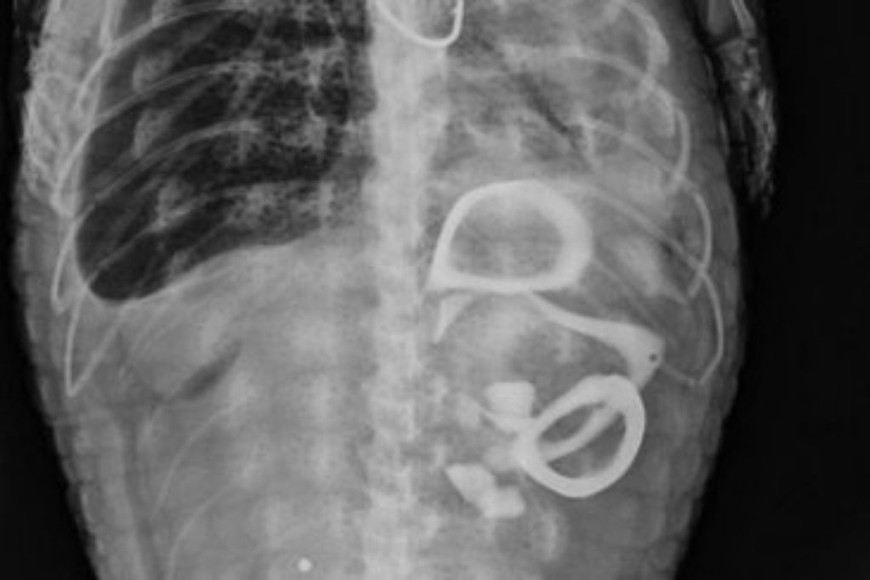

Divulgaron también una radiografía de la caja toráxica del yacaré, donde se visualizan varios elementos ingeridos.

Gentileza Radiografía del yacaré